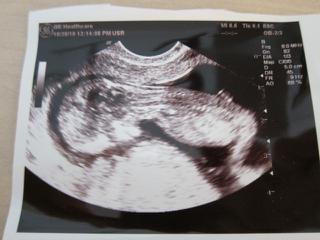

vcera sme boli na sone, videli sme s muzom nasho drobceka, ma 5 cm, cely cas sa hybal, plaval, mrvil sa, no aktivny cela mama, 😀 doktor nam vsetko poukazoval, aj sme videli prsteky na rukach, este nimi babo aj hybalo, aj srdiecko sme videli ako bilo, vsetky merania dopadli dobre, tak sa obaja tesime.

podla sona som na zaciatku 12 tt a podla MS v 14 tt.

A hodim sem aj fotecku, babo bolo otocene, tak davam dve fotky, my s muzom tam vidime aj ucho, oko a usta. 😀

inak zhodli sme sa s mm ze to vyzera na chlapca, podla tej foto z profilu, ale mohli by sme sa mylit, 😉